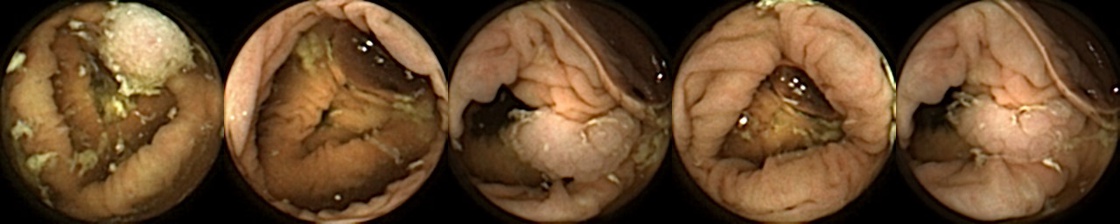

Figure 3 shows classification output examples for the MIV model using the pretrained ConvNext. Note that the model has a test accuracy of 83.66% for DBA L2 with 2 heads. In each row, the leftmost image is the query and the four images to the right of each query are the target images. The True Positive (left-top) and True Negative (bottom-right) examples outline the cases when the model is able to successfully distinguishes images containing unique polyps from those with dissimilar polyps. The False Negative (top-right) and False Positive (bottom-left) examples show the cases where the model fails to correctly distinguish images of unique polyps and images of dissimilar polyps. Further, we can note from the differences in the examples of True Positives and False Negatives that when the query image and the target set instances differ from each other in some ways, then the model can misclassify images. These differences could be attributed to different views due to the dynamics of the camera inside the colon, different views from two camera heads of the capsule, or presence of artifacts such as bubbles, debris, and small bowel secretions.

On the other hand, when we look at the examples of False Positives (Pred = true, Label = false) in Figure 3, we can note that if images in the target match the query in ways such as texture, color, illumination conditions, presence of artifacts, then this may lead to misidentification of the query as belonging to the targets. For True Negative (Pred = false, Label = false) examples, we can see that presence of significant differences between the query and the targets leads to correct identification of the image sets as different.

Figure 3: True Positives (Pred = true, Label = true), False Negatives (Pred = false, Label = true), False Positives (Pred = true, Label = false), True Negatives (Pred = false, Label = false) for the DBA L2(h=2) model using the pretrained ConvNeXt. In each row, the leftmost image is the query and the 4 images to the right of each query are the target images.